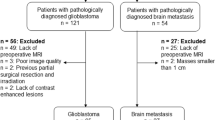

In this prospective study carried out between March 2003 and November 2003 a 3.0-T MR unit was used to perform proton MR spectroscopy, diffusion imaging, and conventional MR imaging on 26 patients with solitary brain tumors (14 high-grade gliomas and 12 metastases). Twelve perfusion MR studies (8 high-grade gliomas and 4 metastases) were also performed. The 26 patients (12 men and 14 women; 25–76 years of age) with untreated solitary brain tumors underwent MR imaging. The presence of the high-grade glioma or metastases was histologically verified by means of either stereotactic biopsy or surgical resection. All of the 14 high-grade gliomas were glioblastoma multiforme. Of the 12 patients with biopsy-confirmed metastases all were carcinomas, 9 were from known primary (2 breast, 5 lung, 2 stomach) and 3 from an unknown primary site. Informed consent for MR examination was obtained from all patients.